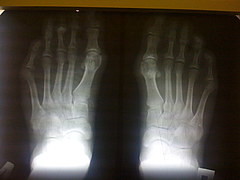

Деформация переднего отдела стопы в виде «Косточки»(Вальгусное отклонение 1-го пальца стопы) – одна из самых распространенных ортопедических проблем, и чаще всего она встречается у представительниц прекрасного пола. У мужчин данная патология встречается значительно реже.

К сожалению, у прекрасной половины человечества часто встречается деформация стоп, в виде шишки у основания большого пальца стопы.

На фоне косметического дефекта, они часто болят, ограничивают продолжительность ходьбы и вызывают трудности при подборе обуви. К счастью, современные хирургические техники, которыми обладают ортопеды, и фиксаторы, которыми хирург надежно скрепляет отломки костей, позволяют в короткие сроки реабилитировать пациентов. Уже в первый день после операции можно ходить в специальной обуви! При этом гипс не накладывается!